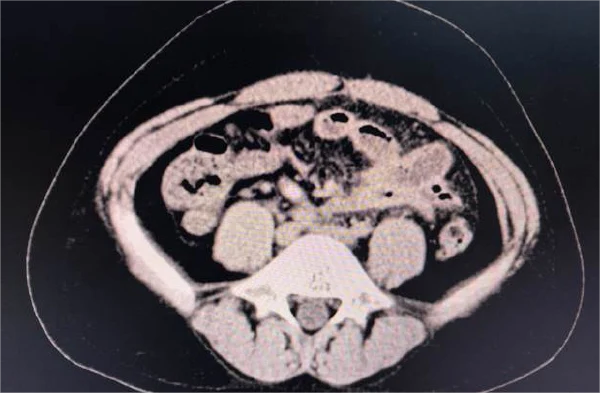

根据给出的检查报告和检查结果,这位患者被诊断为阑尾炎,并接受了阑尾切除术。阑尾炎是一种常见的急腹症,很多人都有可能遭遇。通过手术切除阑尾可以有效治疗此疾病,但术后的恢复和注意事项同样十分重要。此次手术中患者接受了静吸复合麻醉,并进行了粘连松解术。在此报告中,也记录了术前用药和麻醉药物的使用情况,如依托咪酯、丙泊酚、罗库溴铵、舒芬太尼等。手术顺利完成,但术后护理和注意事项对于患者的恢复同等关键。

目前,阑尾炎的治疗方法主要有两种:药物保守治疗和手术治疗。药物保守治疗主要用于症状轻微且初次发作的患者,通过抗生素等药物控制炎症。但绝大部分阑尾炎患者还是需要通过手术治疗,即进行阑尾切除术(Appendectomy)。

手术方法有传统的开放手术和腹腔镜手术两种。腹腔镜手术因创伤小、恢复快而被广泛采用,但在某些复杂病例中,可能需要采用开放手术。手术过程中,麻醉师会根据患者的情况选择合适的麻醉方法,确保手术顺利进行。术后,通过抗生素治疗和细致的护理,患者可以较快恢复。